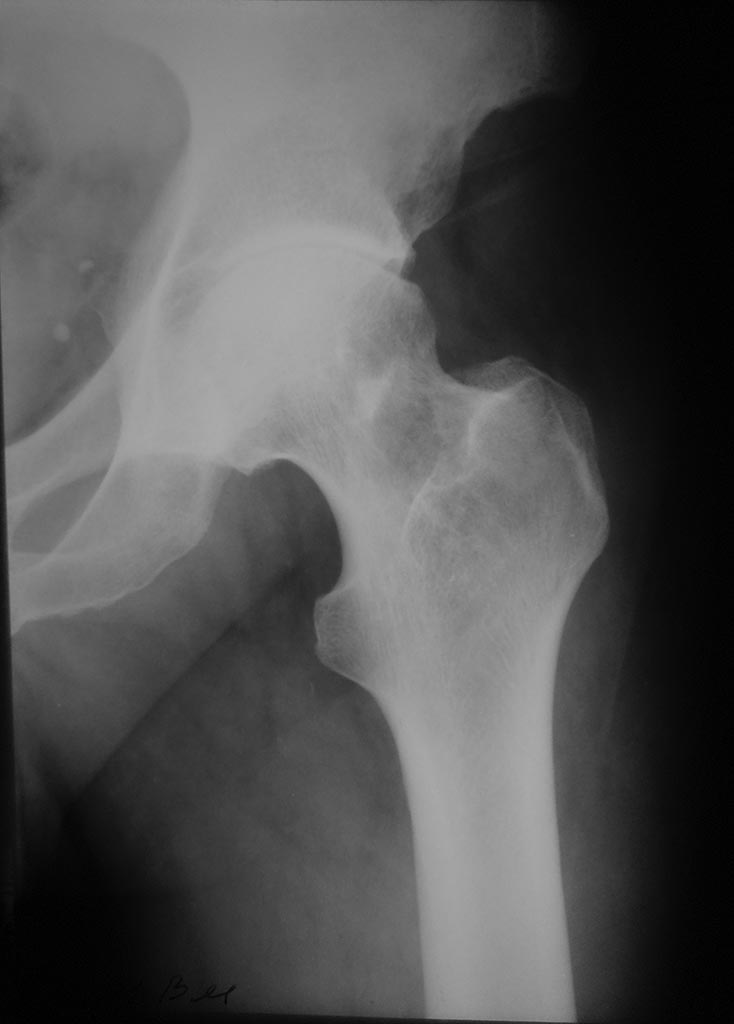

Неясный диагноз ТБС

Резкая отрицательная диамика на РГ за 2 мес